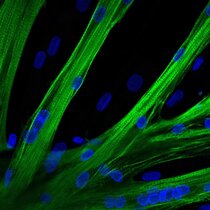

Mutationen, die zu Muskelschwund führen, lassen sich mit der Genschere CRISPR/Cas9 reparieren. Ein Team um die ECRC-Forscherin Helena Escobar hat das…